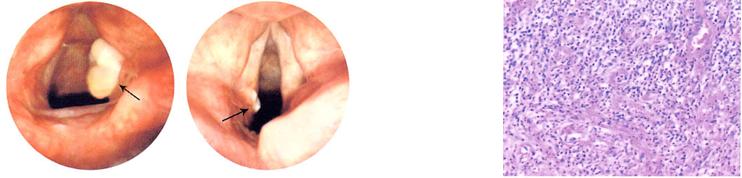

喉接触性肉芽肿是是多发生于声带后1/3杓状软骨声带突附近的非瘤性炎性肉芽组织,大部分为单侧发病,偶有双侧同时发生,约占嗓音疾病的0.9%~2.7%,Jackson于1928年首次报道此病。

箭头所指即喉接触性肉芽肿

LCG的形成是由于各种诱因导致声带突黏膜破损并发炎性反应,甚至可侵及软骨膜。组织活检病理检查提示鳞状上皮增生或伴溃疡、角化,周围见大量肉芽组织和急慢性炎性细胞聚集。有学者表明因为缺乏单核或多核细胞的浸润,所以其并不是一种真正的肉芽肿疾病,而是人体组织损伤后的一种代偿修复过程,而这个过程需要经历4个阶段:出血、炎性反应、增生及重塑,所以LCG是一个非瘤性的炎性肉芽组织。

肉芽组织内可见大量炎性细胞浸润和毛细血管增生 HE×100